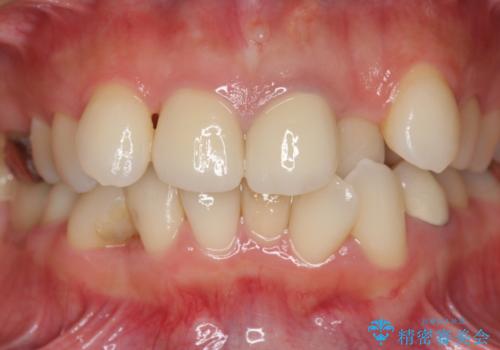

子供の頃にぶつけた前歯 根管治療から行うセラミック治療

- 26万円(仮歯・ファイバーコア・ジルコニアクラウン×2)費用は治療当時の料金となります